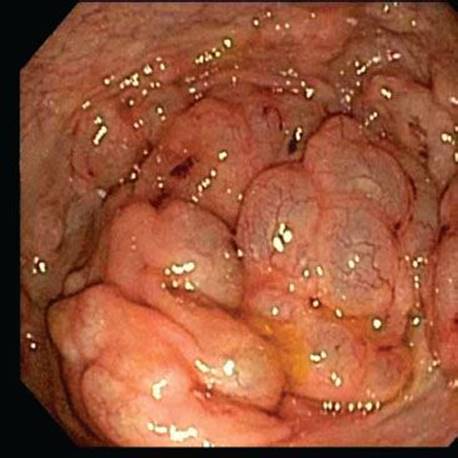

Figure 4.257 PCI, endoscopic image. Corresponding endoscopic images of the bowel wall show numerous convoluted mucosal folds that appear almost cerebriform.

Figure 4.258 PCI, endoscopic image. An alternate view of the same case shows similar features. The bowel wall is distended with large air pockets.